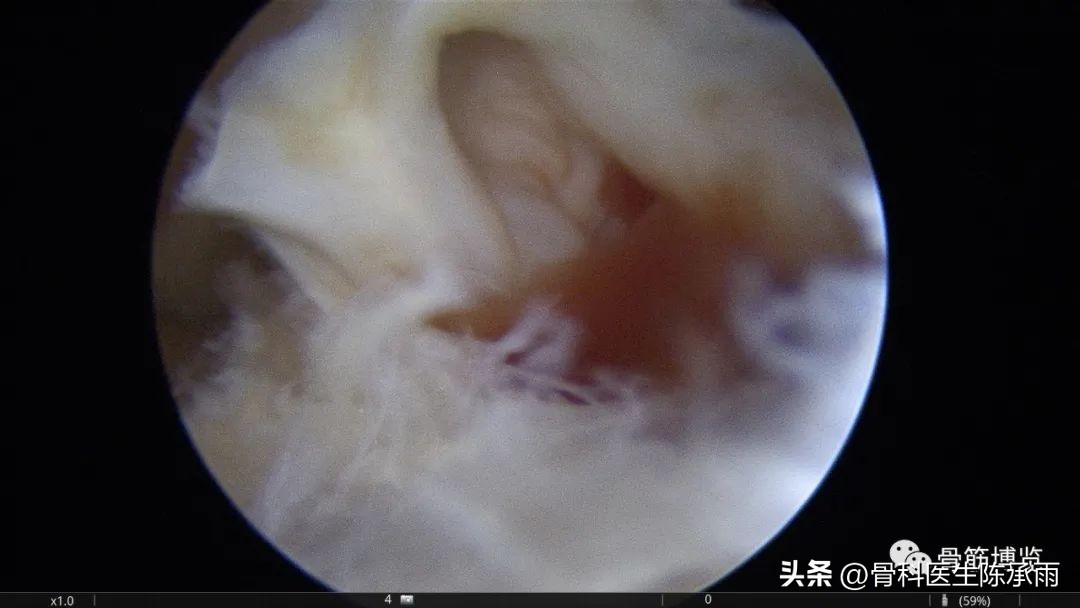

本例为内侧半月板前角巨大囊肿,关节镜下行半月板囊肿引流减压+囊肿前壁及囊壁滑膜切除+半月板缝合术。术中切除全部囊壁内滑膜及前壁及大部分后壁,保留部分后壁组织,以保证半月板前角缝合可靠及稳定。

术中情况

半月板囊肿分型决定了治疗方法的选择,对于前两种半月板囊肿因伴有半月板的损伤治疗方法相对复杂,半月板囊肿合并的半月板损伤多为水平撕裂或复杂撕裂,而且病史较长,因此需严格掌握缝合手术的指证。手术操作要点:采用常规的髌下内侧和髌下外侧入路,探查关节内囊肿和半月板撕裂的大致范围;使用刨刀细致地将囊肿切除,尽量彻底切除囊壁,充分敞开囊腔,避免囊肿复发,囊肿内可有分房或分隔现象,注意避免遗漏。注意在手术时尽量保留冠状韧带,避免冠状韧带的广泛缺损;进一步仔细探查损伤的半月板组织,明确撕裂的范围在红﹣红区或红﹣白区,对于超出上述范围的损伤或半月板的复杂撕裂及水平撕裂,放弃缝合手术,如条件许可时可在切除部分半月板(如切除水平撕裂的两片中不稳定的一片)的基础上进行缝合手术。然后以刨刀或磨钻小心修整损伤的半月板组织,使对合面整齐并显露新鲜组织;髌下外侧人路置人工作套管,附加经髌韧带的正中入路,严格解剖复位。经正中人路置人探针,固定半月板撕裂部位,使用肩袖缝合器经髌下外侧入路工作套管,缝合器尖端首先由半月板前缘和冠状韧带的交界处穿人半月板下表面后,越过半月板裂隙,在对侧由下到上穿出半月板上表面,经工作套管将线导出,体外打 Duncan 结,推线器将线结推人至半月板前缘处拉紧,再打两个套结,剪断缝线。两缝线之间间距8 mm 。滑膜囊肿的手术操作相对简单:镜下切除囊肿后,将半月板与冠状韧带之间的缺损区缝合。